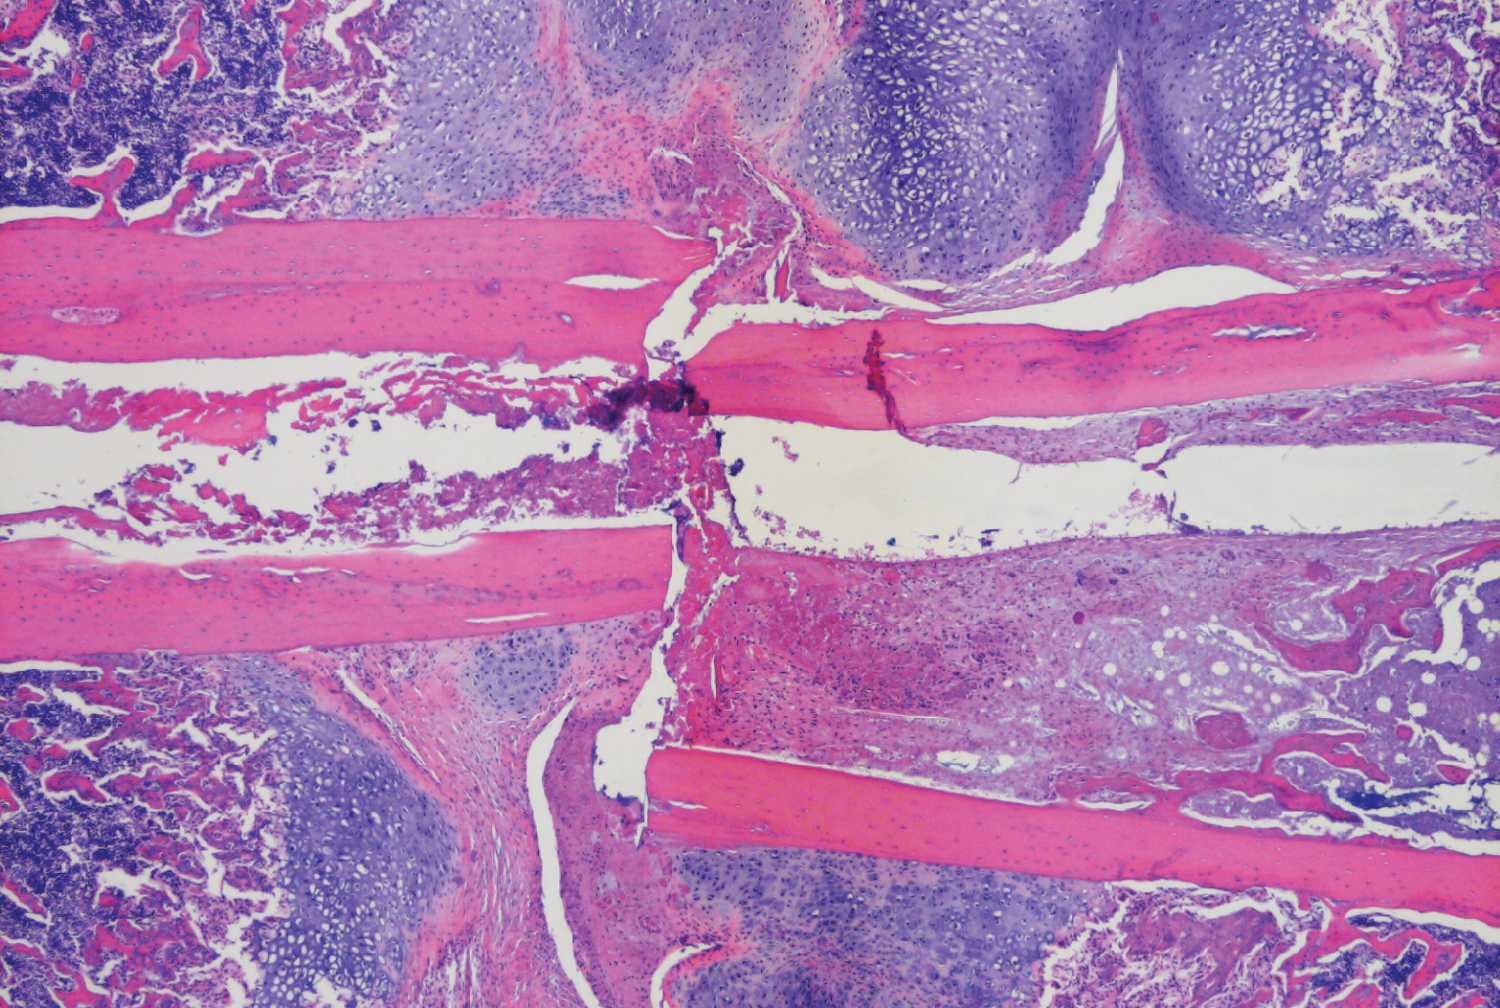

To counteract that trend, Dr. Greenblatt has been investigating the cellular causes of osteoporosis in an effort to promote bone growth. Prior research using mice genetically engineered to lack an adaptor protein known as SHN3 showed that its absence conferred high bone mass. Building on that discovery, Dr. Greenblatt and his team decided to examine the resulting changes in bone blood vessels. “We used those mice as a means to find the signals coming from osteoblasts to control the specific type of blood vessels present in bone,” he said.

The researchers were surprised to find that osteoblasts secreted unchanged amounts of almost all known factors promoting blood vessel growth, but SLIT3 levels rose significantly. And when the mice were genetically altered to delete SLIT3, they exhibited low bone mass. “We next asked if we could use SLIT3 to treat mice with skeletal disease, especially osteoporosis and fracture healing,” Dr. Greenblatt said. “When we gave the rodents SLIT3, it reversed their osteoporosis and made their fractures heal faster and stronger.”

In addition to benefiting seniors with osteoporosis, Dr. Greenblatt hopes his research will also help patients with bone injuries that aren’t healing properly, such as those who’ve undergone orthopedic surgery or have fragile bones due to genetic diseases. “Some of those people’s fractures don’t heal because they can’t grow the right type of blood vessels at the site of the fracture,” he said. “That’s what we think SLIT3 will do: help with that growth and promote healing.”